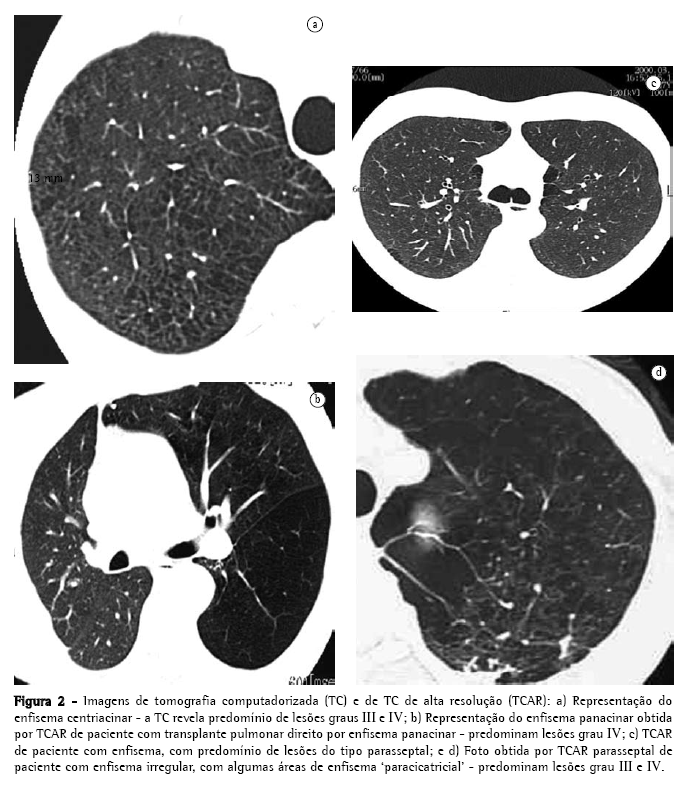

Em 1958,(13) publicou-se um artigo de grande importância por apontar erros na preparação dos espécimes pulmonares para entendimento das lesões enfisematosas, descrevendo melhores técnicas de distensão e fixação. Em revisão de trabalhos anteriores,(6) uma autora assim definiu os parâmetros anatomopatológicos, conforme sua distribuição em relação ao ácino, (Figura 2): centroacinar, parasseptal ou periacinar, panacinar, e irregular.

O tipo centroacinar, como o nome sugere,acomete a porção central do ácino, junto aos bronquíolos respiratórios. Há dilatação seletiva, com confluência dos elementos centrais no ácino, principalmente os bronquíolos respiratórios e seus alvéolos. O processo tende a ser mais acentuado nos terços superiores dos lobos superiores e inferiores. O enfisema centroacinar está fortemente associado ao tabagismo e à bronquite crônica, com predomínio no sexo masculino. As alterações inflamatórias nas pequenas vias aéreas são comuns, com entupimento, infiltrado mural e fibrose, levando a estenose, bloqueio do fluxo de ar, além de distorção e destruição da anatomia do centro do ácino.

O tipo parasseptal só ocorre naqueles ácinos delimitados pelo tecido conjuntivo, sejam septos conjuntivos periféricos, pleuras e bainhas de tecido conjuntivo, peribrônquicas ou perivasculares. Apresenta uma tendência em se desenvolver onde as margens pulmonares são regulares. Os espaços aéreos no enfisema parasseptal freqüentemente se tornam confluentes e se desenvolvem em bolhas, que podem ser grandes. Acredita-se que o enfisema parasseptal seja a lesão básica na doença pulmonar bolhosa.(14) A obstrução de via aérea e o distúrbio respiratório são freqüentemente menores no enfisema parasseptal, apesar da grande formação de bolhas.

O enfisema do tipo panacinar acomete o todo dos ácinos, com dilatação e destruição de seus alvéolos. As características que usualmente diferenciam os alvéolos dos dutos alveolares estão perdidas, os poros de Kohn aumentam, e desenvolvem-se fenestras entre os alvéolos. Este processo tem sido comparado a uma simplificação difusa da arquitetura do pulmão. Com a destruição progressiva, tudo o que finalmente resta são finas bandas de tecido cercando vasos sangüíneos. O enfisema panacinar é o tipo de enfisema mais disseminado e grave e, conseqüentemente, o que mais resultará em doença clinicamente significativa. As alterações patológicas estão distribuídas no todo dos pulmões, mas, com freqüência, a distribuição é predominantemente nos terços inferiores. O tipo de enfisema que ocorre na deficiência de alfa-1-antitripsina, na síndrome de Swyer-James e em casos de enfisema familiar, é predominantemente do tipo panacinar. Apesar de ser considerado o enfisema dos não-fumantes, também ocorre induzido pelo tabagismo, em associação com enfisema centrolobular. Quando o enfisema encontra-se às margens de uma cicatriz nos pulmões, pode ser denominado como enfisema paracicatricial ou irregular. A classificação em enfisema irregular é reservada aos casos onde não é possível classificá-lo nos outros três tipos.

Além da classificação conforme a distribuição em relação ao ácino, ressalta-se a necessidade de graduar as lesões enfisematosas, para que se tenha uma noção da gravidade da doença do ponto de vista anatomopatológico. Esta graduação é necessária, especialmente no enfisema do tipo panacinar e do tipo centriacinar.

Evolução da imagética na investigação e quantificação do enfisema Em contraste com o radiograma convencional de tórax, a tomografia computadorizada (TC) tem-se mostrado muito sensível e específica na avaliação do enfisema.(14,23-43) Desde que os achados foram descritos pela primeira vez em 1982,(14) a TC tem sido empregada para detectar, caracterizar e quantificar a doença. O enfisema centrolobular caracteriza-se pela presença de áreas de baixa atenuação, com margens mal definidas, geralmente sem paredes visíveis.(44) As lesões conferem um aspecto similar ao de tecido roído por traças. Quando as lesões enfisematosas atingem diâmetros maiores que as do ácino, parte de suas margens podem se tornar bem definidas, simulando cistos, devido à presença de septos intersticiais, ou vasos maiores margeando as lesões. Em um estudo que avalia vários sinais de enfisema centrolobular, as áreas de baixa atenuação na medular dos pulmões, demonstradas na TC, se correlacionaram significativamente com enfisema avaliado post mortem.(45) Outros sinais de enfisema incluem bolhas (pseudocistos que contêm ar, com paredes finas bem definidas), rarefação de vasos, e distorção da vasculatura. Os sinais complementares de hiperinsuflação dos pulmões que, quando acentuados, são prontamente identificados no radiograma de tórax, podem não ser tão óbvios na TC. Entretanto, a linha de junção anterior dos pulmões, medindo 3 cm no sentido ântero-posterior, é sugestiva de hiper-expansão no paciente com enfisema.(46)

A TC de alta resolução (TCAR) é capaz de diferenciar entre os vários tipos de enfisema, em pacientes com doença leve ou moderada,(47) retratando com grande semelhança os achados da anatomia patológica acima descritos, onde o enfisema centrolobular apresenta: predileção pelos terços superiores,(45) podendo estar confinado a estas regiões; áreas de baixa densidade multifocais decorrente da destruição dos alvéolos, com predomínio na medular, distantes da pleura(45); lesões que podem se assemelhar a pequenos espaços aéreos císticos, geralmente sem uma parede óbvia; e pulmão circundante às lesões, que pode ser totalmente normal. Com a progressão da doença, as lesões centrolobulares enfisematosas se tornam confluentes.

A TCAR, no enfisema panacinar, demonstra destruição pulmonar mais uniforme, com extensas áreas de baixa densidade, acompanhadas de distorção e rarefação vascular. No enfisema panacinar puro, não são encontradas pequenas áreas focais de baixa densidade, características do enfisema centrolobular. Em contraste com este último, a distribuição é preferencial nos terços inferiores dos pulmões.

O enfisema parasseptal é facilmente detectado na TCAR, e apresenta-se como áreas de baixa densidade, bem delimitadas por paredes finas, com espessura semelhante a fios de cabelo.(48) Esses pseudocistos distribuem-se nas regiões subpleurais ou adjacentes a feixes broncovasculares maiores. Este padrão de enfisema, curiosamente, lembra dentes de uma serra e, ocasionalmente, os septos intersticiais podem parecer particularmente proeminentes; algumas vezes, podem simular linfangite carcinomatosa no radiograma de tórax, o que é prontamente diferenciado à TCAR.(48)

Alguns autores(39) estudaram a quantificação por escore visual, com escala de 1 a 5, conforme acometimento de 0, 25, 50, 75% ou 100% dos pulmões. A correlação desta técnica com a anatomia patológica apresenta correlação de r = 0,91 in vitro (com espécimes pulmonares de cadáveres). In vivo, esta correlação é de r = 0,81.(24-39)Deve-se considerar, contudo, que existem limitações naturais quando se utiliza a análise subjetiva para a quantificação do enfisema, seja por método radiológico, seja por avaliação pela macroscopia ou microscopia, na anatomia patológica.

Na tentativa de diminuir a subjetividade inerente à técnica utilizada por um autor, outros autores(31) propuseram a estratificação visual em classes, por meio do auxílio de grades superpostas à imagem de TC, a qual apresenta boa correlação anatomopatológica; porém, é demasiadamente trabalhosa e bastante subjetiva. O nível e a abertura da janela na escala de unidades Hounsfield (UH), selecionados para a análise da imagem de TC, podem influenciar significativamente na identificação de áreas de enfisema.(29-34) A melhor seleção de janela para a identificação visual do enfisema é aquela que utiliza abertura incluindo 1100 UH, e com nível ou centro fixo em -750 UH. Outra limitação comum às duas técnicas é a falta de consenso sobre o número mínimo de cortes tomográficos necessários para que a quantificação seja representativa do todo dos pulmões. Além destes problemas, relata-se que a corrente do tubo também influencia significativamente na identificação visual subjetiva do enfisema à TCAR.(39)